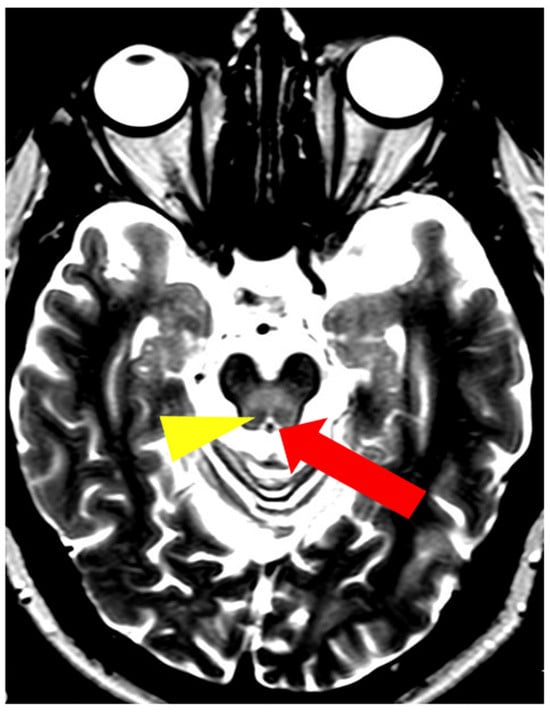

5. Neuroradiological Pathognomonic Signs of WD

- Hitoshi, S.; Iwata, M.; Yoshikawa, K. Mid-brain pathology of Wilson’s disease: MRI analysis of three cases. J. Neurol. Neurosurg. Psychiatry 1991, 54, 624–626. [Google Scholar] [CrossRef] [PubMed]

- Vella, S.; Grech, R. Highlighting an atypical cause of the Face of the Giant Panda sign. BJR Case Rep. 2018, 4, 20170046. [Google Scholar] [CrossRef] [PubMed]

- Sonam, K.; Bindu, P.S.; Gayathri, N.; Khan, N.A.; Govindaraju, C.; Arvinda, H.R.; Nagappa, M.; Sinha, S.; Thangaraj, K.; Taly, A.B. The “double panda” sign in Leigh disease. J. Child. Neurol. 2014, 29, 980–982. [Google Scholar] [CrossRef] [PubMed]